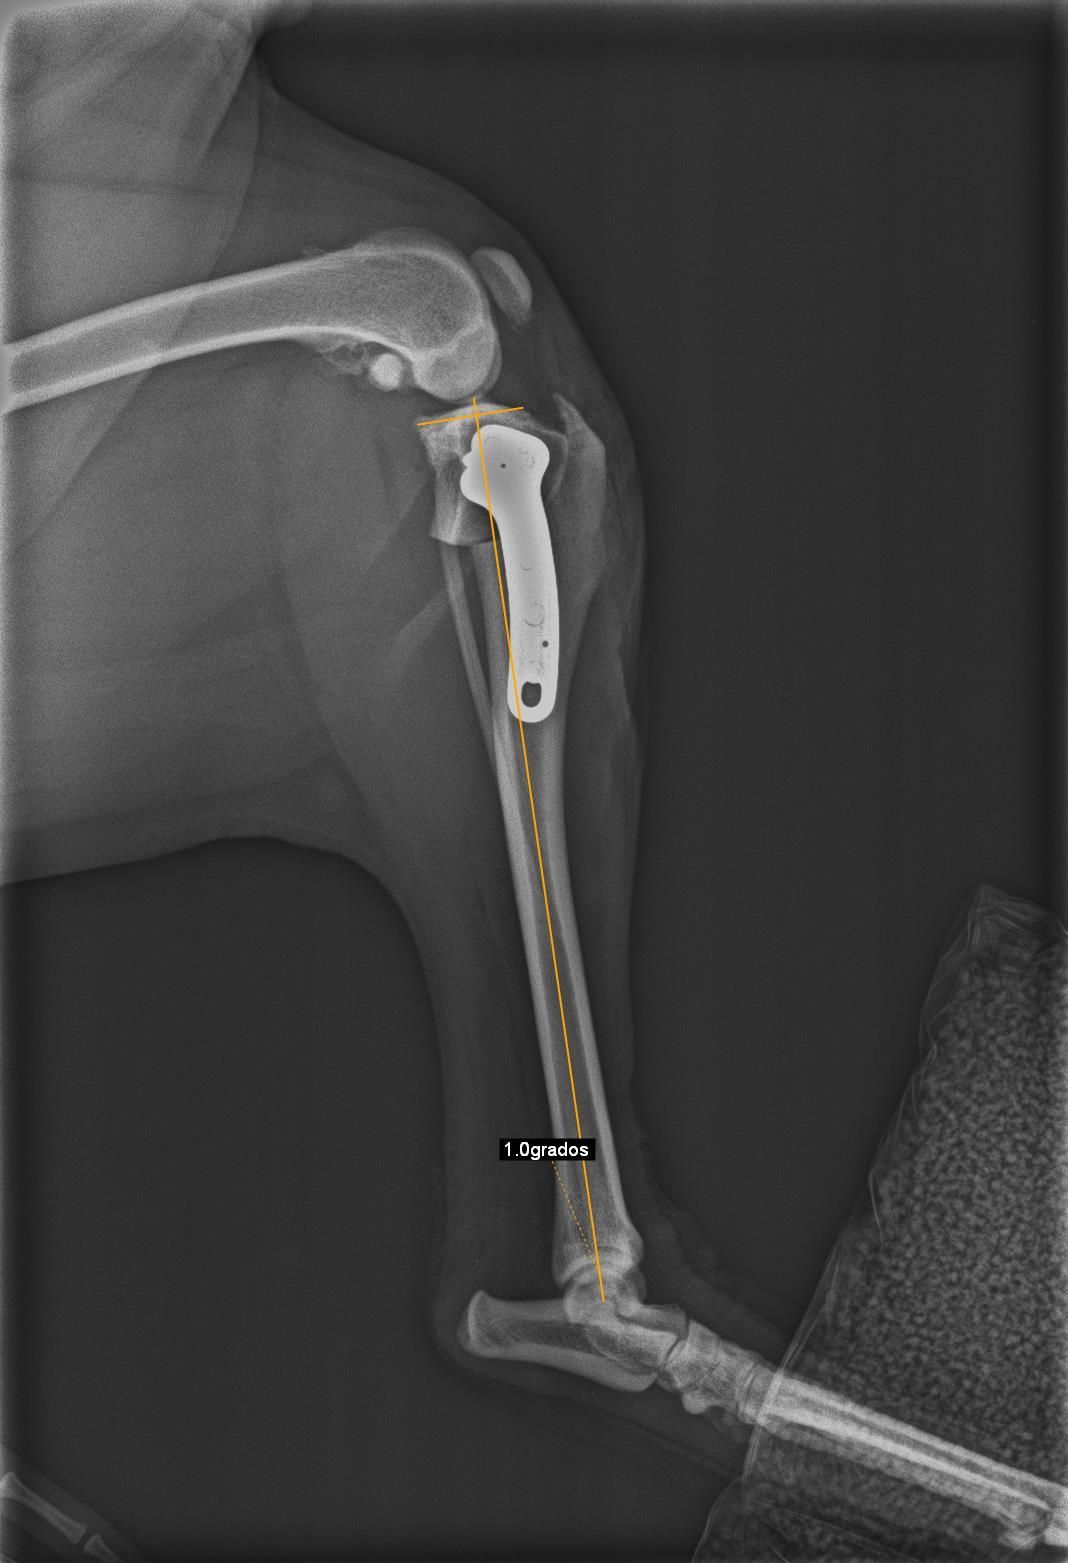

TPLO

La TPLO (Tibial Plateau Levelling Osteotomy) y la TWO (tibial wedge ostectomy) son otras técnicas de resolución de rotura de ligamento cruzado muy eficaces en perros de gran talla.

Consiste en hacer un corte en la tibia y nivelar la meseta tibial, aplicando una placa especial que hace que el ligamento cruzado no sea necesario, ya que se neutralizan la fuerzas de empuje tibial.